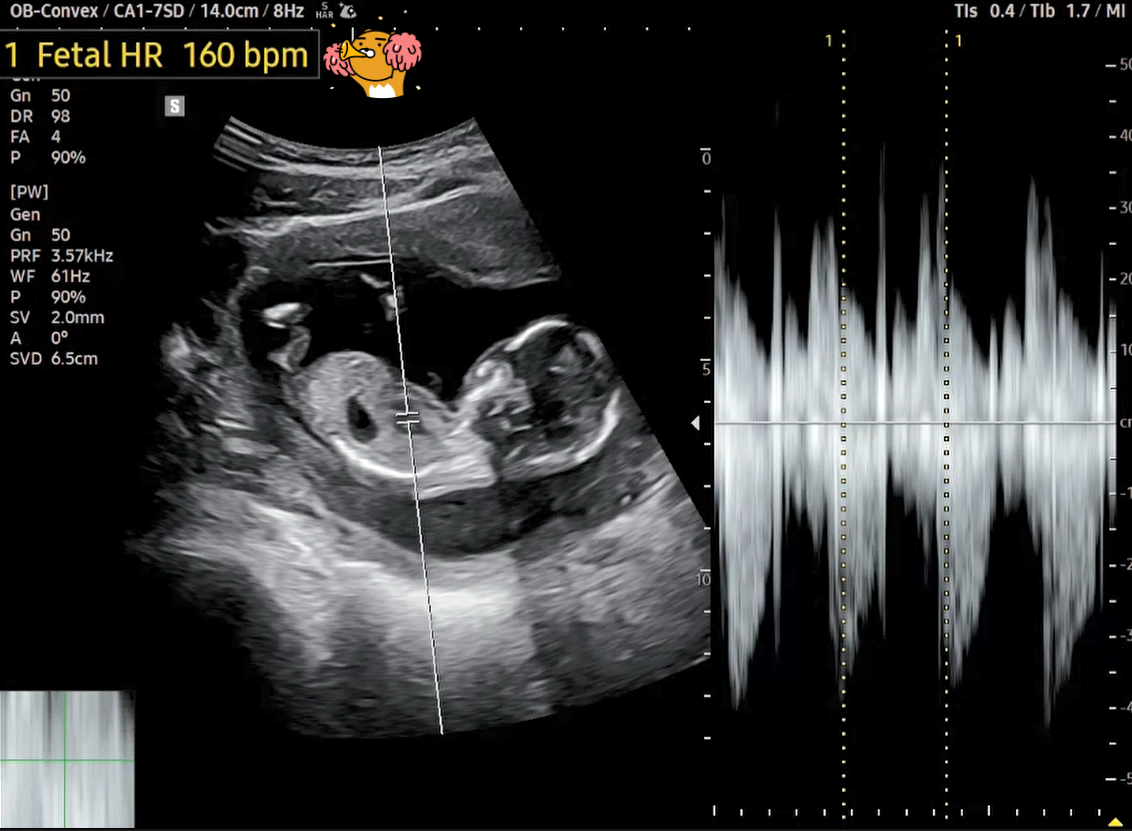

급하게 병원 진료를 받으면서, 태아의 상태도 초음파로 확인하였다고 합니다.

딸애가 보내준 초음파 사진을 보고, 우리 '팡팡이'가 잘 자라고 있는지 나름 확인을 해보았습니다.

14주 차 태아는 머리부터 아래까지 대략 8.5cm 정도로, 키위 한 알 정도의 크기라고 하네요. 머리 모양도 점점 더 둥글어지고, 몸의 나머지 부분과 비례하여 커진다고 합니다. 또한 눈꺼풀이 발달하고 손가락과 발가락에 손톱과 발톱이 생기는 시기이기도 하답니다. 그리고 태아의 심박수도 평균 160회/분이며, 이후 매주 1회씩 느려져 만삭이 되면 120~160회/분 사이로 규칙적인 심박수를 유지한다고 합니다.

초음파 사진을 캡처하여 보니 우리 '팡팡이'의 크기는 8.78cm이고, 심박수는 160 bpm으로 정상이네요.

참고로 GA(Gestational Age)는 임신 주수이며, CRL(Crown-Rump Length)은 태아의 머리부터 엉덩이까지의 길이, Fetal HR(Heart Rate)은 태아 심장박동수를 뜻합니다.

[14주 차 초음파]